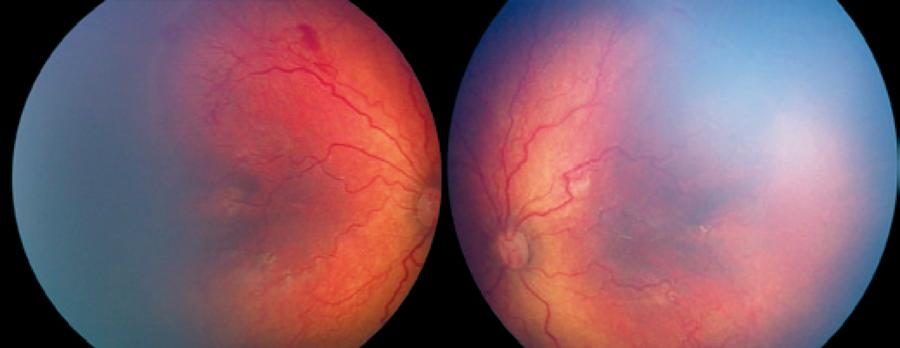

Intravitreal anti-VEGF injections were administered to 36 eyes of 20 patients as first treatment. Fifteen eyes of 8 patients (4 males, 4 females) received ranibizumab injections in group 1. In group 2, 21 eyes of 12 patients (5 males, 7 females) received bevacizumab (Figures 1, 2). The mean gestational time was 26.2 ± 2.7 weeks in group 1 and 27.1 ± 2.5 weeks in group 2. The mean birth weight was 853 ± 120 g in group 1 and 925 ± 110 g in group 2 (Table 1). The mean post menstrual age (PMA) at the time of injection was 34.4 ± 1.8 weeks in group 1 and 35.3 ± 1.7 weeks in group 2 (Table 2). Intravitreal anti-VEGF injection was not administered to one eye of one patient in group 1 and three fellow eyes of three patients in group 2 because no progression to type 1 ROP was observed, and ROP had regressed in 1 week in the three fellow eyes of three patients in group 2.

Figure 1 Right and left eyes of a premature baby born at 28 weeks with a 910 g birth weight.

Figure 2 One year after IV bevacizumab injection in the same patient shown in figure 1